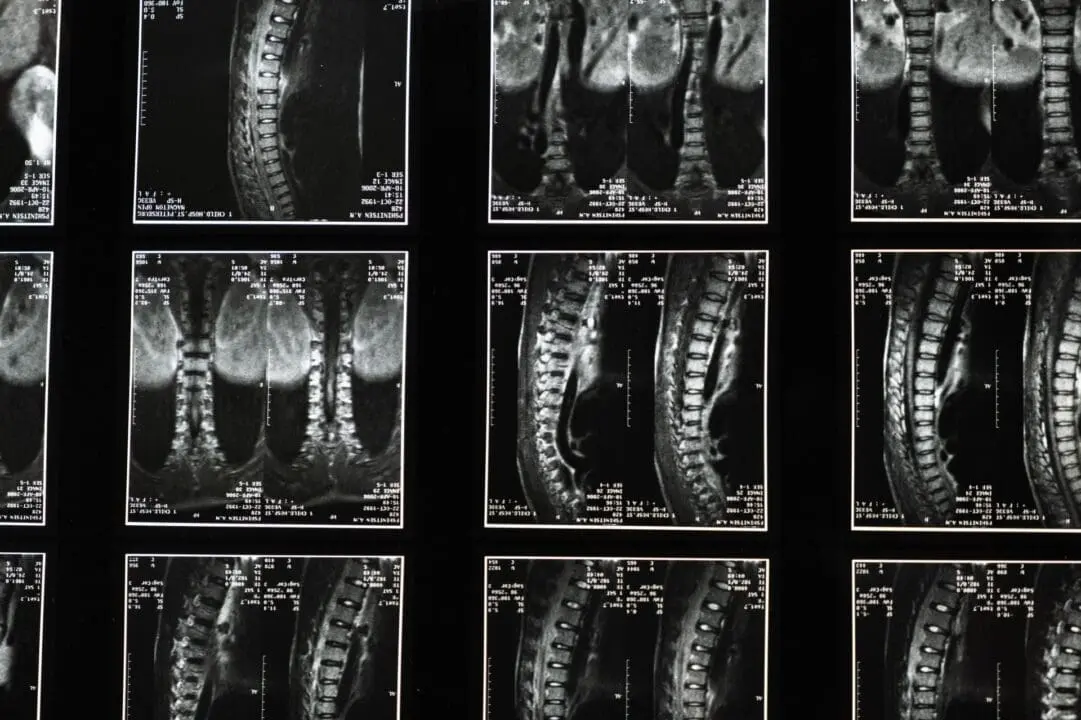

Bone Sarcoma